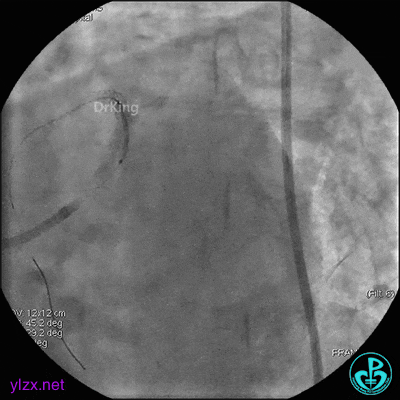

1周后复查造影,见粗大前降支3级血流,近端严重狭窄伴管壁严重钙化影,病变累及前降支开口。

球囊扩张后前降支中段植入支架。

前降支近端串联植入支架,前降支开口支架精确定位。

支架内非顺应性球囊后扩张。